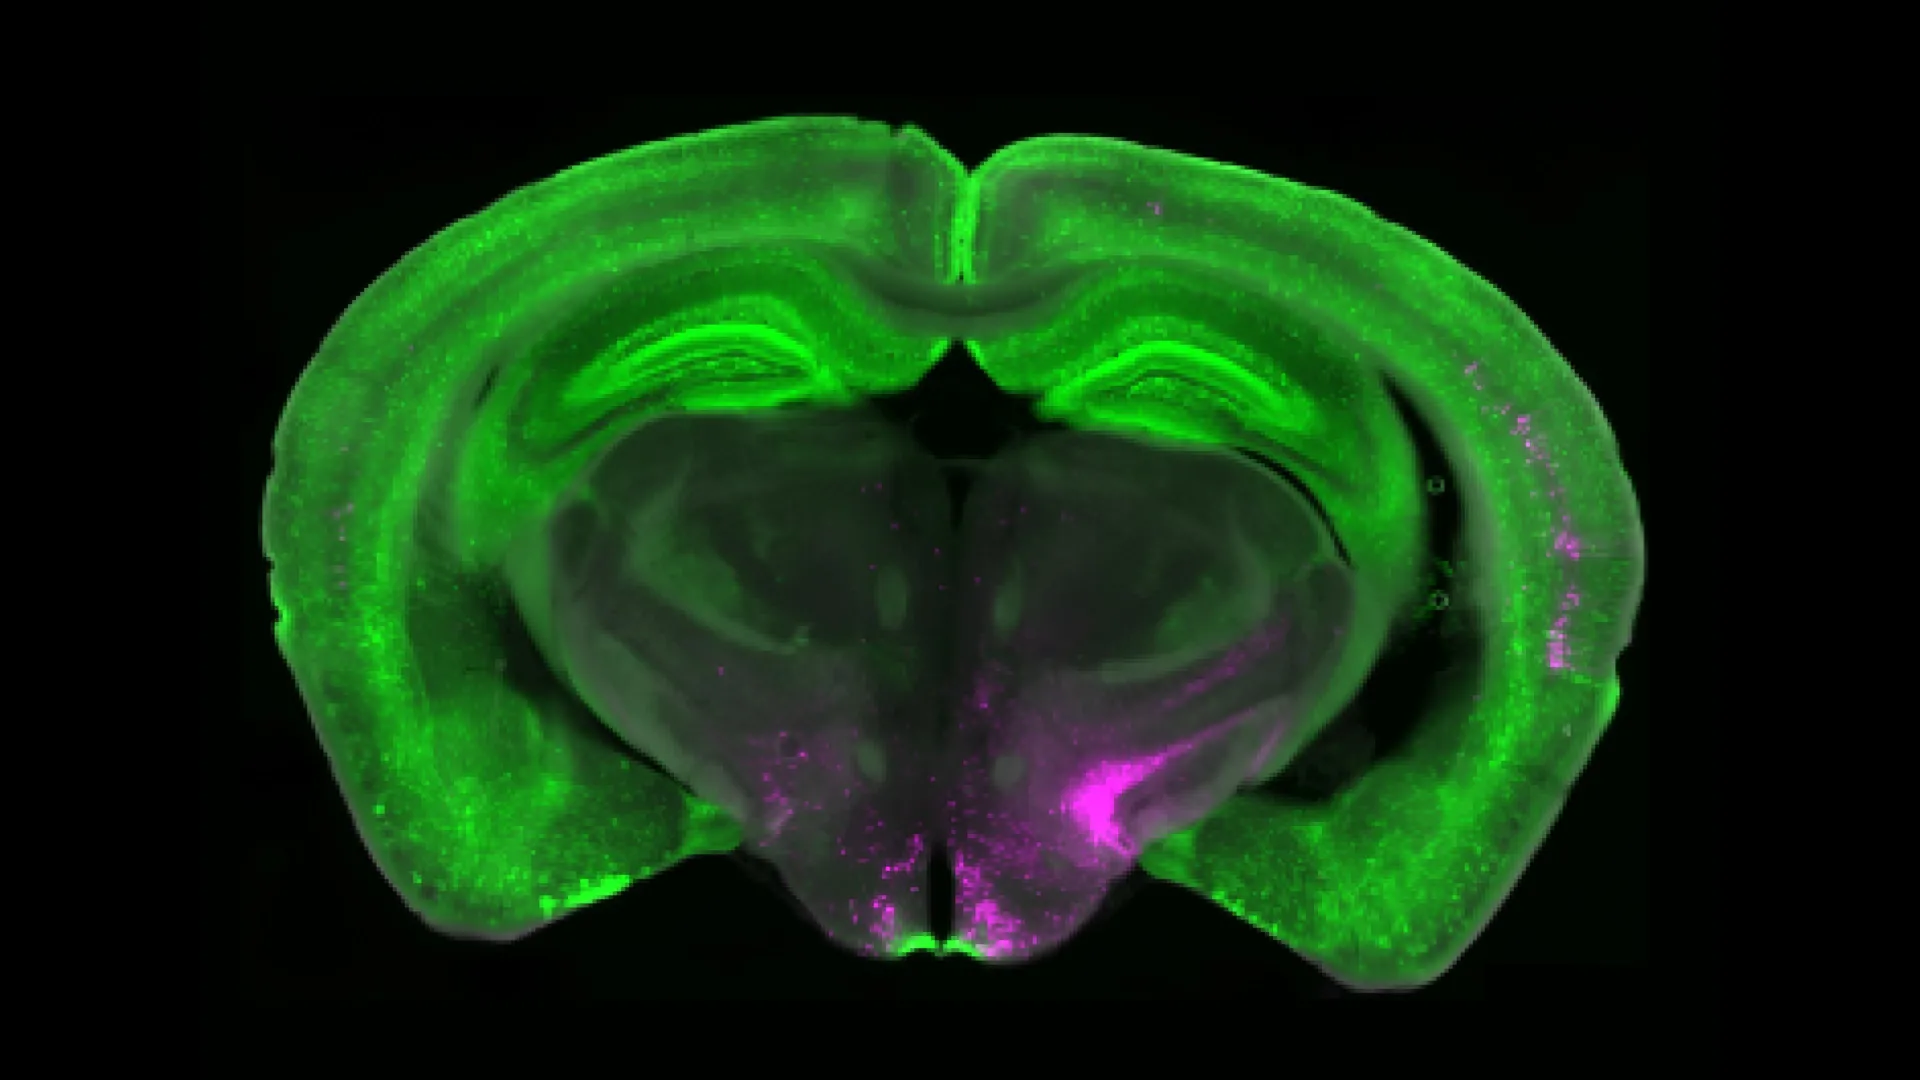

Betley, along with collaborators from the University of Pittsburgh and Scripps Research Institute, has discovered an important piece of the chronic pain puzzle. Their research points to a specific group of brainstem cells called Y1 receptor (Y1R)-expressing neurons, located in the lateral parabrachial nucleus (lPBN). These neurons are activated in persistent pain states, but they also process signals related to hunger, fear, and thirst. This suggests that the brain can adjust pain responses when other, more urgent needs demand attention.

Working with the Taylor lab at the University of Pittsburgh, Betley’s team used calcium imaging to visualize neuron activity in real time in animal models of both short-term and long-term pain. They observed that Y1R neurons did not simply react to quick bursts of pain; instead, they kept firing steadily during prolonged pain, a phenomenon known as “tonic activity.”

The researchers also characterized the molecular and anatomical identity of the Y1R neurons in the lPBN. They found that Y1Rneurons didn’t form two tidy anatomical or molecular populations. Instead, these neurons were scattered across many other cell types.

“It’s like looking at cars in a parking lot,” Betley says. “We expected all the Y1R neurons to be a cluster of yellow cars parked together, but here the Y1R neurons are like yellow paint distributed across red cars, blue cars, and green cars. We don’t know exactly why, but we think this mosaic distribution may allow the brain to dampen different kinds of painful inputs across multiple circuits.”